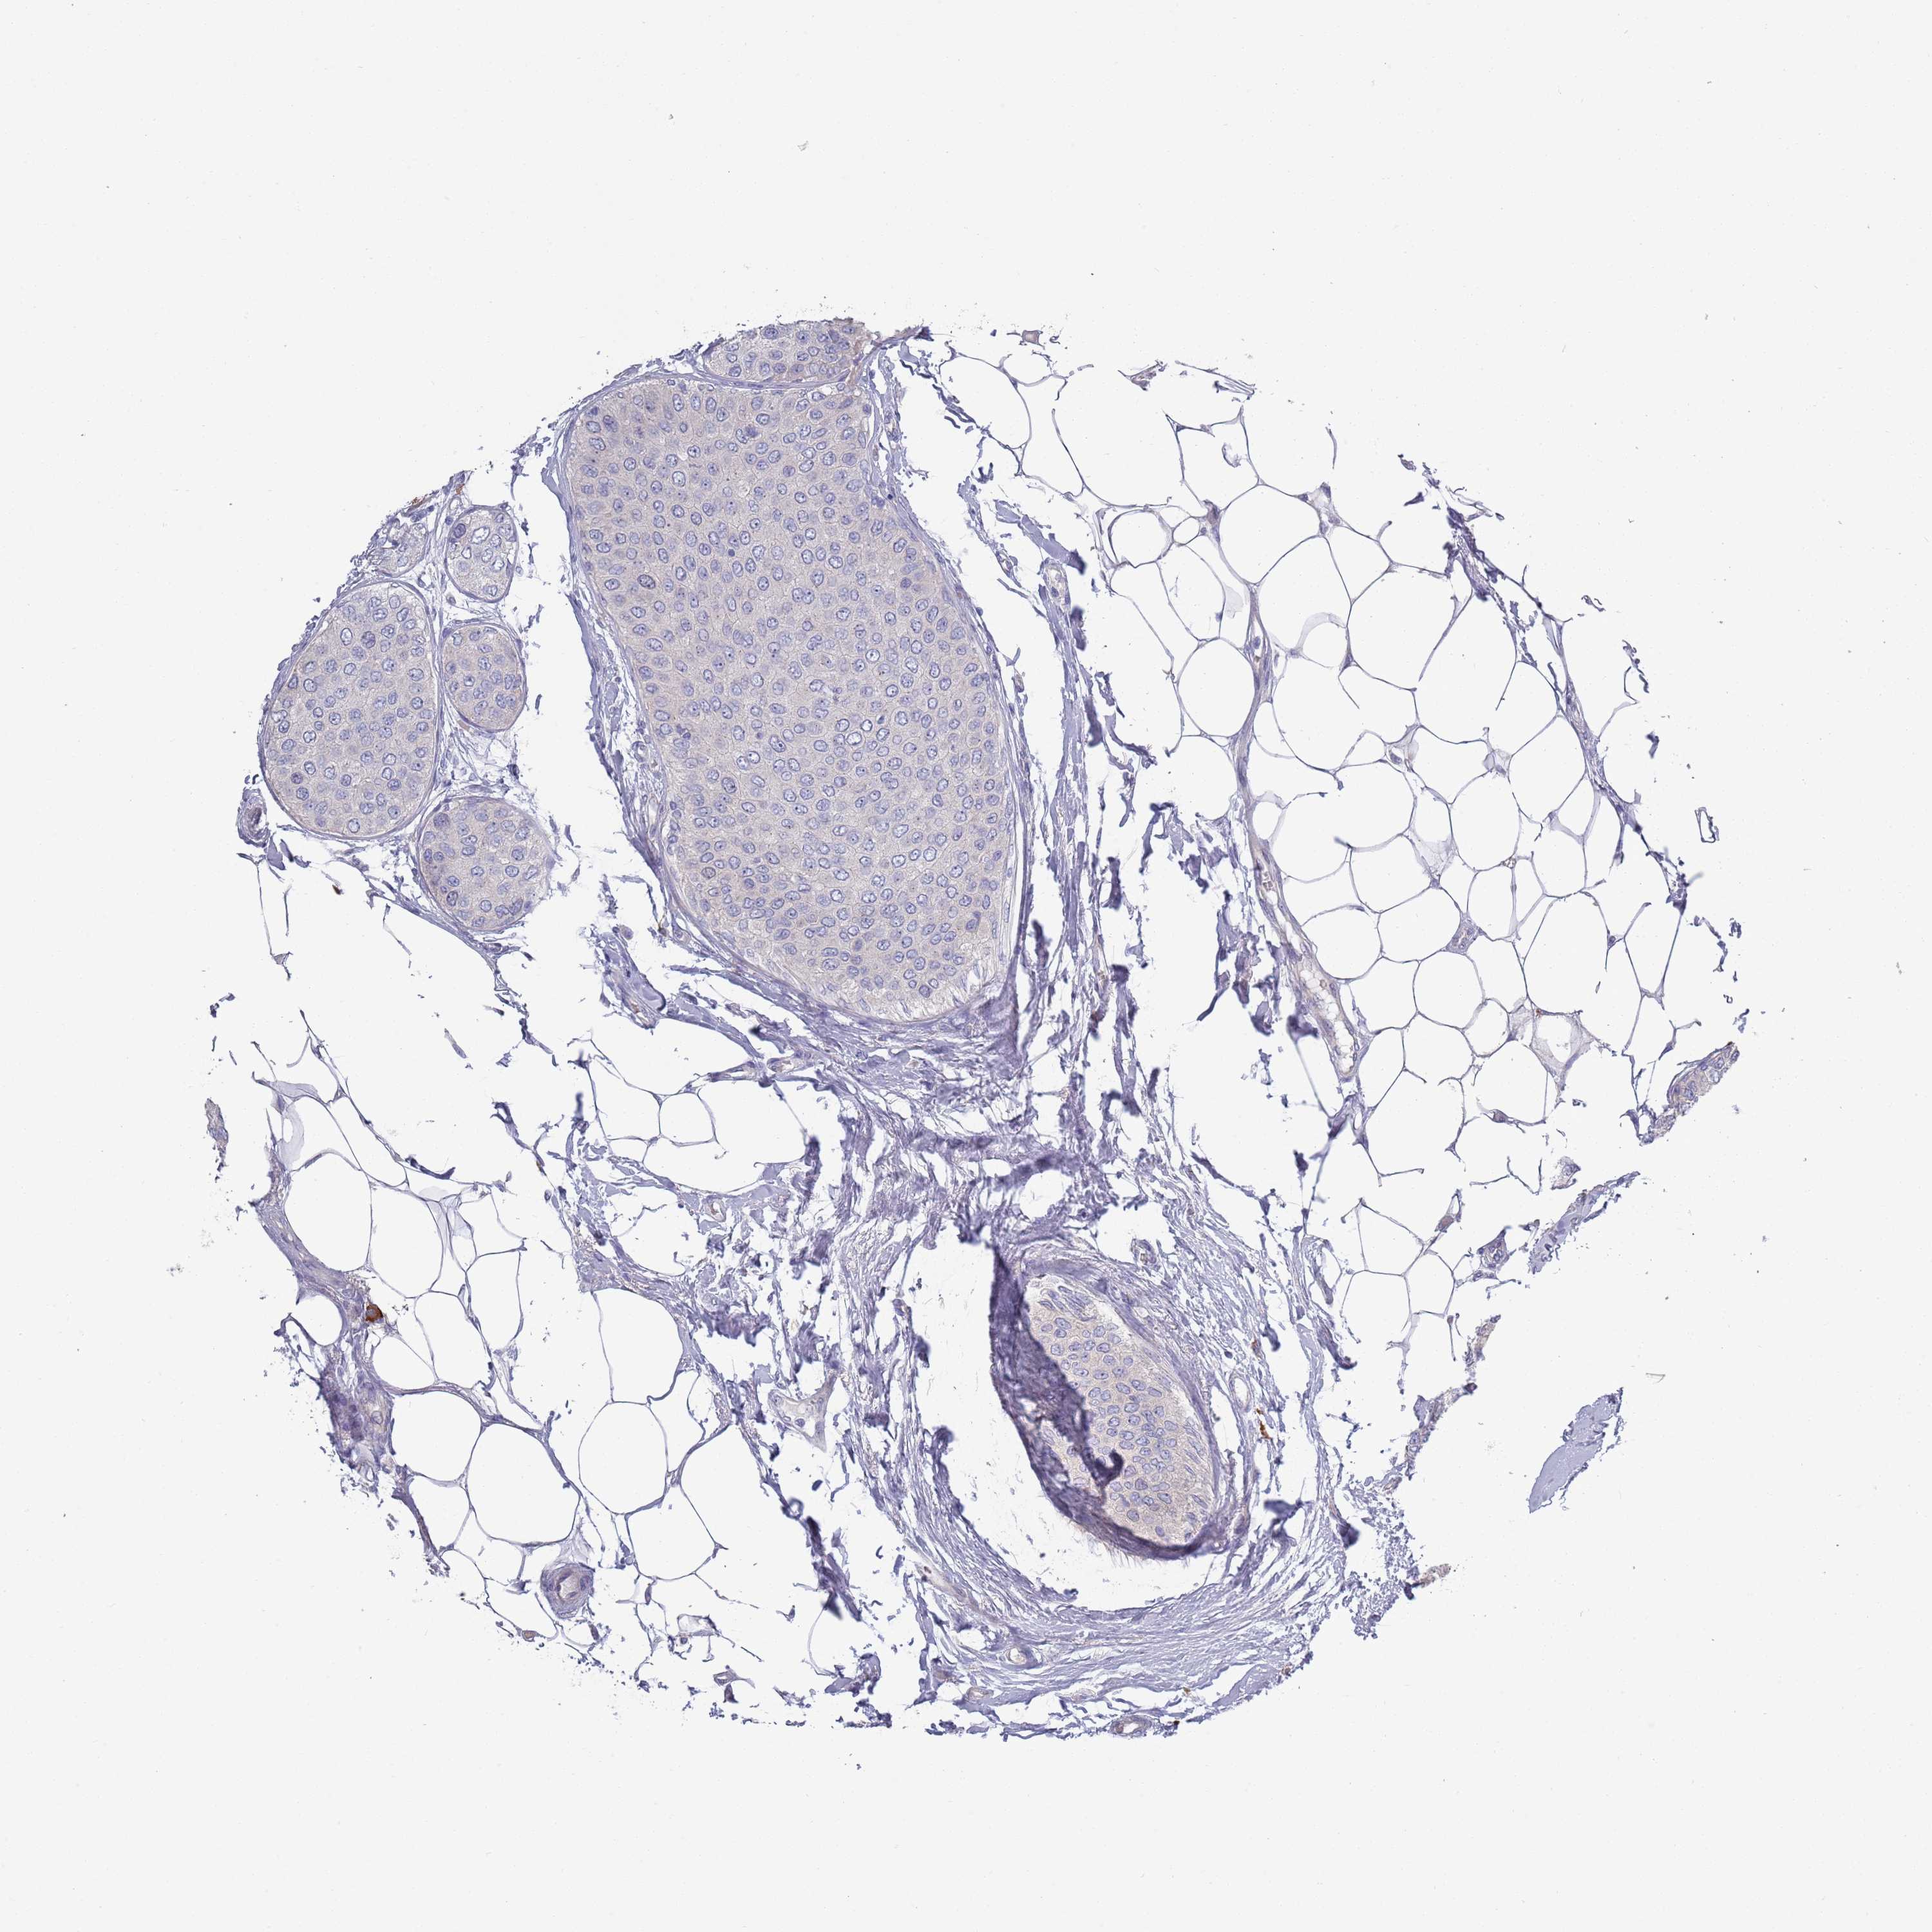

CANCER BREAST CANCER Show tissue menu

BRCA TCGA BRCA VALIDATION PROTEIN EXPRESSION